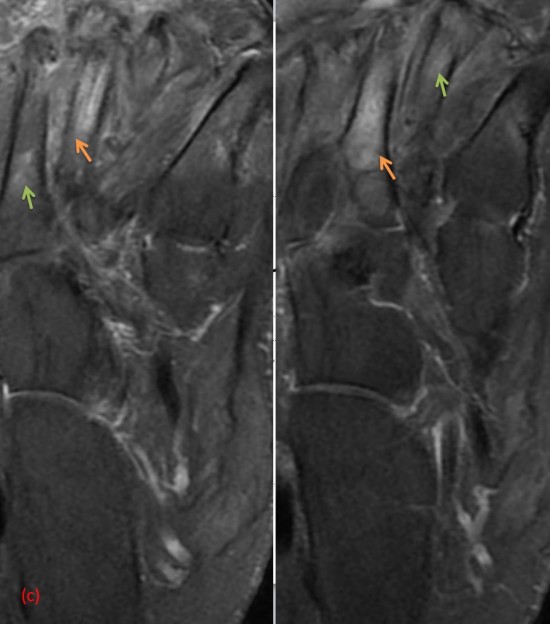

Patient de 44 ans presentant une masse peu sensible de la face palmaire du poignet avec des.

Une anomalie des membres caracterisee par labsence congenitale dun membre a partir du coude. Tumeurs pseudo tumeurs thrombose veineuse ulnaire du poignet irm.